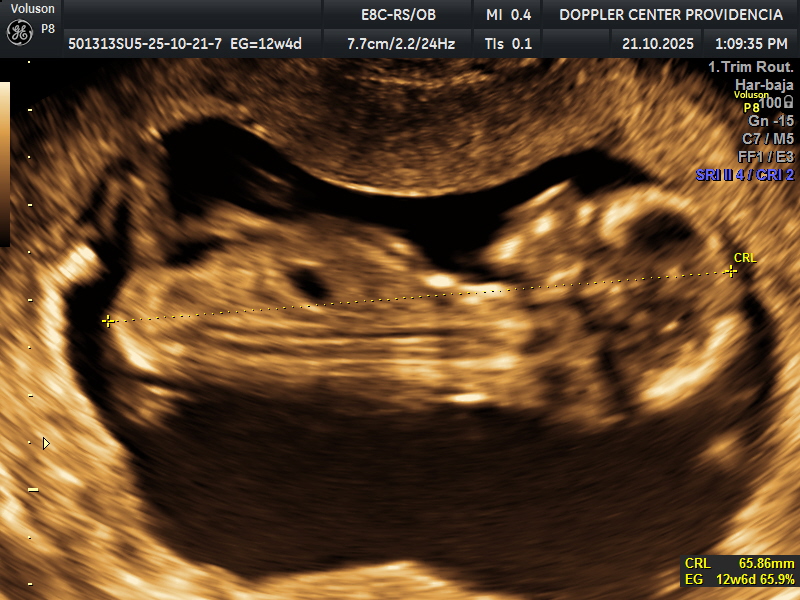

• Eco Doppler 11-14 semanas